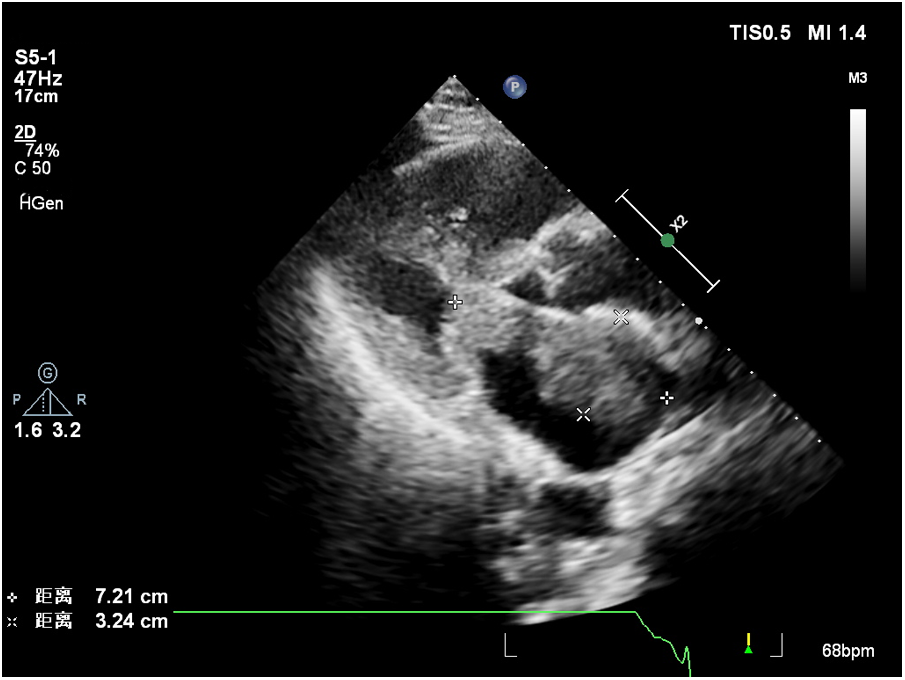

Laboratory results indicated a serum troponin level of 0.043 ng/ml, normal serum creatinine, and an elevated B-type natriuretic peptide (BNP) level of 3,170 pg/ml. A transthoracic echocardiogram revealed two masses in the left atrial cavity. The larger mass measured 7.2 × 3.2 cm and was located proximally to the mitral valve. The smaller lesion measured 2.5 × 2.4 cm and was directly linked to the mitral valve. The masses were characterized by irregular shapes, clear boundaries, and uneven echogenicity. During diastole, the small mass prolapsed into the left ventricular inflow tract, generating a 35 mmHg pressure differential. The transthoracic echocardiogram also found mitral orifice obstruction with mild regurgitation; moderate pulmonary hypertension; mild tricuspid regurgitation; small amount of pericardial effusion, Pressure difference halved time 149 ms, and no significant abnormalities were observed in the residual valves. Some specific data is shown in Table 1. Based on ultrasound findings, a preliminary diagnosis of a left atrial mass was made, with suspicion of malignancy.

Contrast-enhanced echocardiography was recommended, revealing rapid perfusion of the contrast material into the right and left atria and ventricles. After a few cardiac cycles, the mass was substantially enhanced, almost matching the surrounding myocardium, confirming the likelihood of a malignant tumor (Figure 1, Supplementary Video 1).

Figure 1

The larger mass close to the mitral valve.

Left atrial myxofibrosarcoma is usually characterized by low or moderate echogenic masses attached to the left atrial valve or wall (3). These lesions often exhibit unclear boundaries from surrounding normal tissue, irregular shapes, and uneven echogenicity. Additionally, they are frequently large, sessile, and possess a broad base. They may also invade the pulmonary veins and exhibit other features. In the present case, one of the masses oscillated around the mitral valve orifice during the cardiac cycle, obstructing the valve orifice during diastole. This resulted in symptoms of mitral stenosis, such as chest tightness and dyspnea. Distinguishing left atrial myxofibrosarcoma from left atrial myxoma is crucial. The American Society of Echocardiography guidelines recommend the differentiation of intracardiac masses using ultrasound enhancement agents (8). Benign cardiac tumors, predominantly myxomas, typically exhibit sparse neovascularization, with the myxoid matrix composed of acidic mucopolysaccharides (9, 10). In contrast, malignant tumors, such as myxofibrosarcomas, grow rapidly and feature abundant new blood vessels, densely distributed with a dilated lumen, resulting in significant enhancement during angiography (11). Of note, conventional ultrasonography revealed that the mass had an irregular shape, uneven echogenicity, no peduncle, and a wide base, which required differentiation from a thrombus. Of note, thrombi do not exhibit enhanced imaging due to a lack of blood vessel supply, a feature distinguishing them from malignant tumors (8, 12). Postoperatively, a follow-up transthoracic echocardiography was conducted 8 months later, unveiling the recurrence of the tumor in the left atrium. Further characterization through contrast-enhanced ultrasound indicated sparse enhancement of the left atrial mass, with the degree of enhancement lower than that observed in the surrounding myocardium.